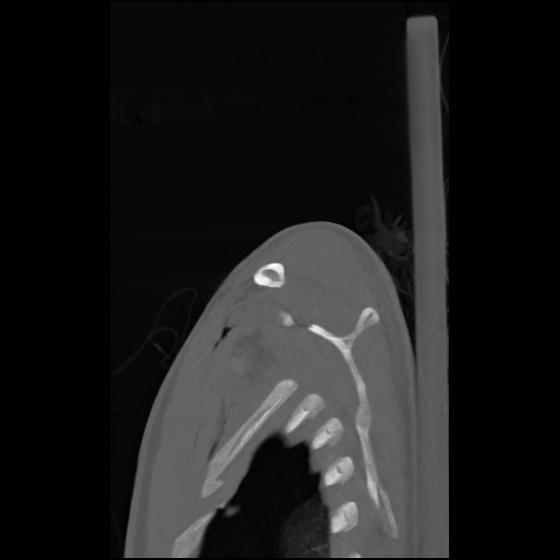

24 ANGIO,CE,Sag-MIP,5.000,ANGIO,Sag-MIP,